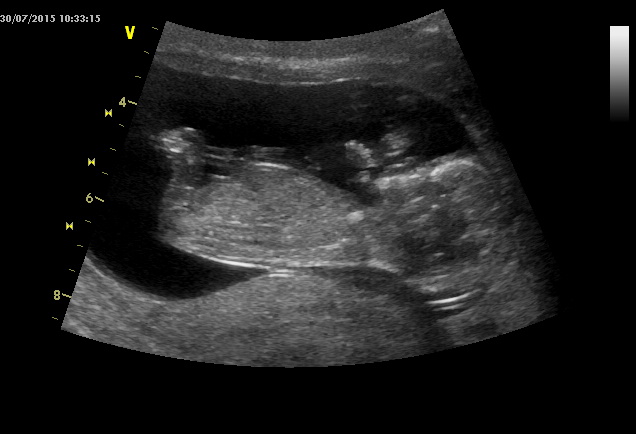

Ahoj holky tak jsme po utz a už to máme na 150% holčičku, měla vaječníky nebo co to :D Ale fotit se nechce Terezka naše, měla hlavu furt v placentě a ne a ne se ukázat má 300g a jsem 19+5 a dle MS 20+1tt ale říkal že tonje normalka fotky nic moc no jak rikam nechtěla se ukázat za celé tehu jsem pribrala 2,1 kg a teď za ty 3 týdny 1,3 kg :D tlak normalka nizsi, přítel no chudak asi ani nevěděl na co se kouká a 3D říkal že je nechutné :D atbmunukazuju jen černobílé :D jinak na další kontrolu 24.11. A na cukr nvm? To asi až pak nebo vůbec?

A tady jsou některé fotky ze screeningů